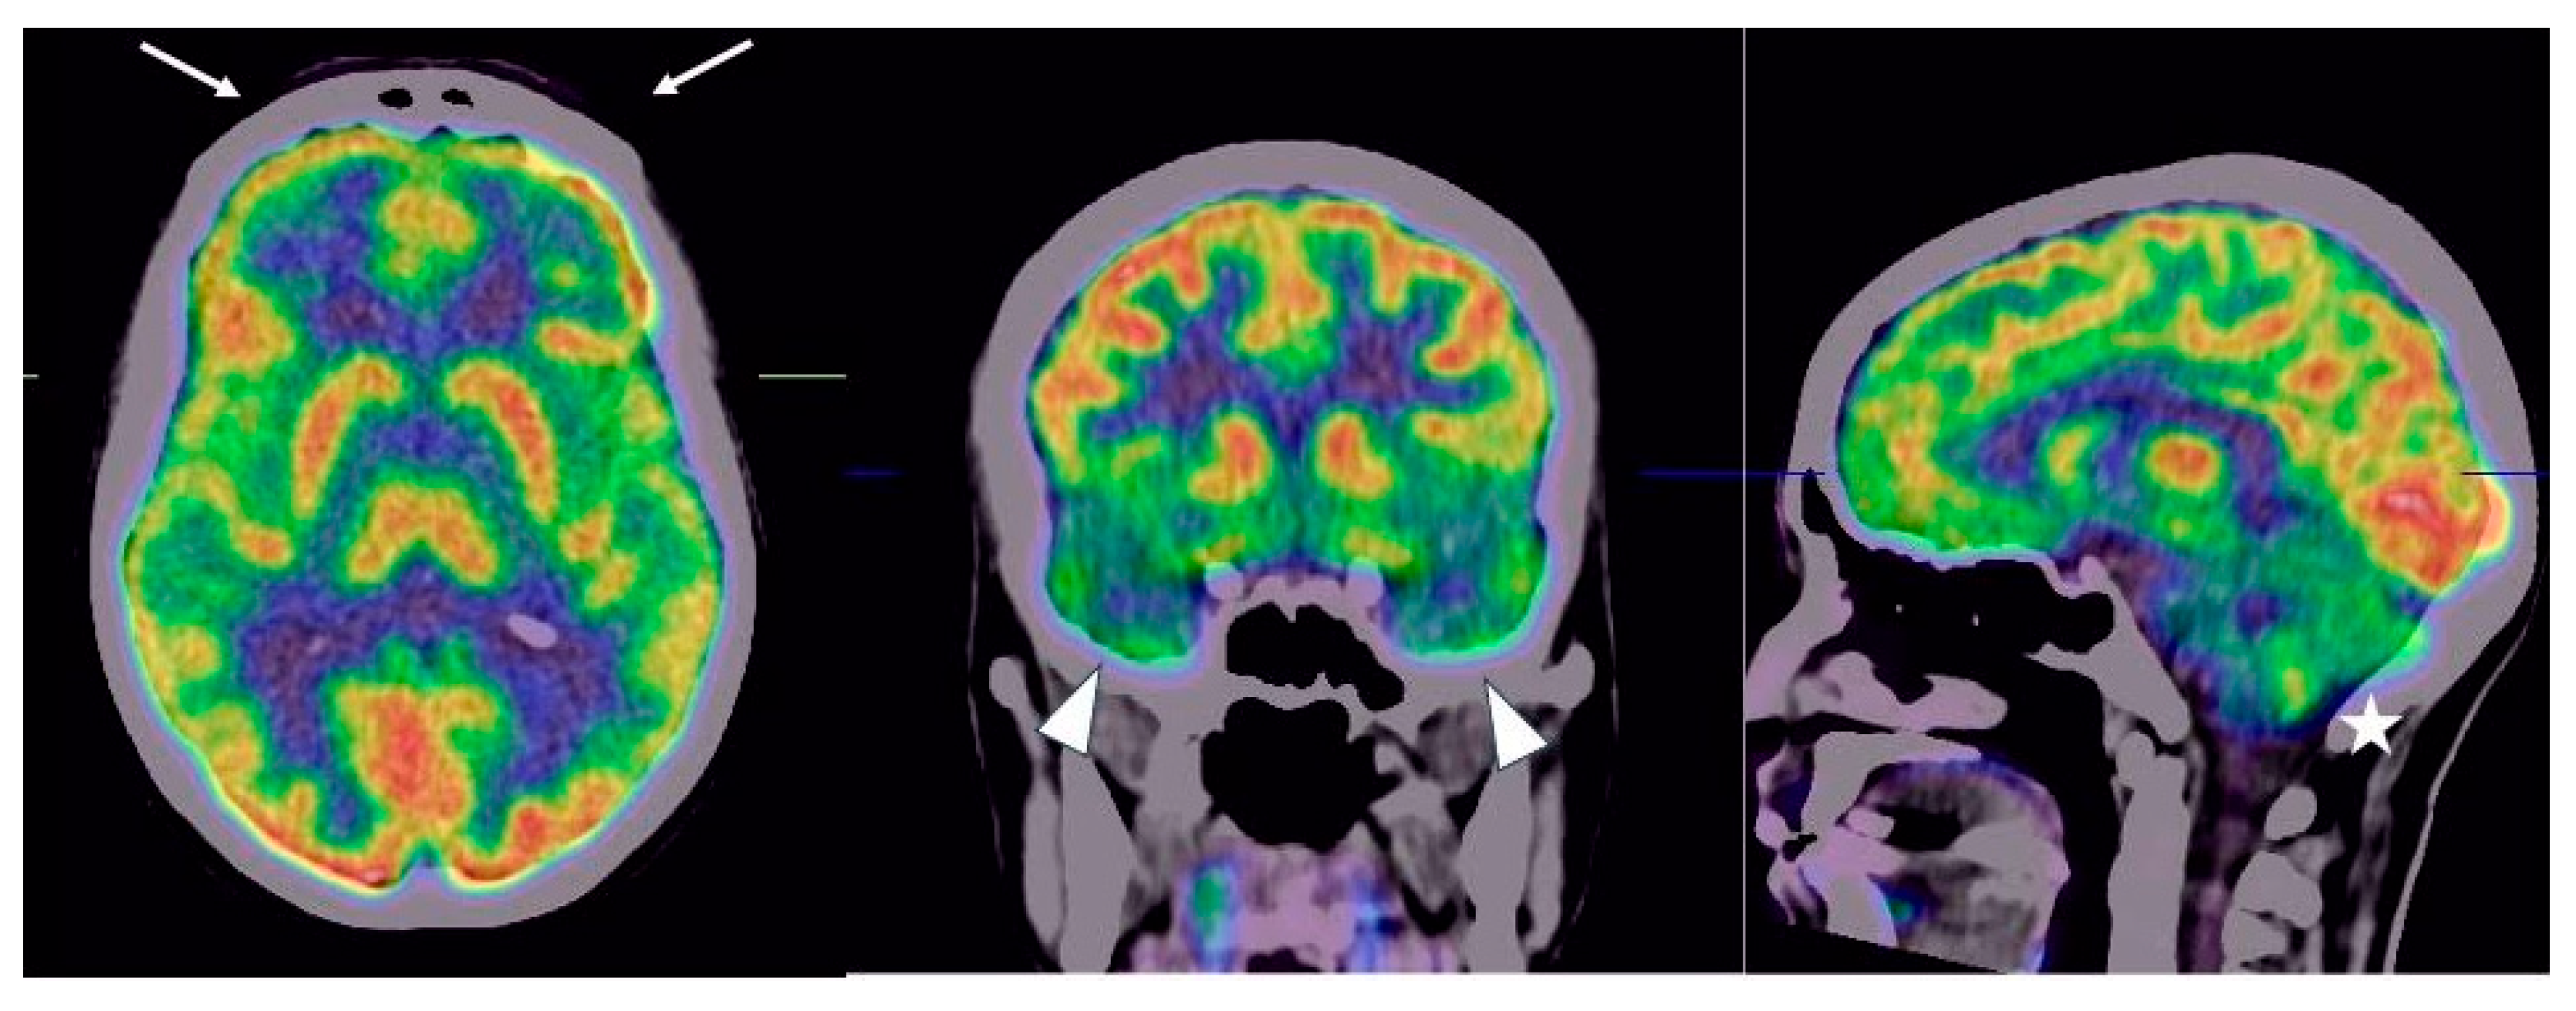

Persistent 18F-FDG Brain PET Fronto-Temporal Hypometabolism and Cognitive Symptoms Two Years after SARS-CoV-2 Infection: A Case Report

2. Case Description

3. Discussion